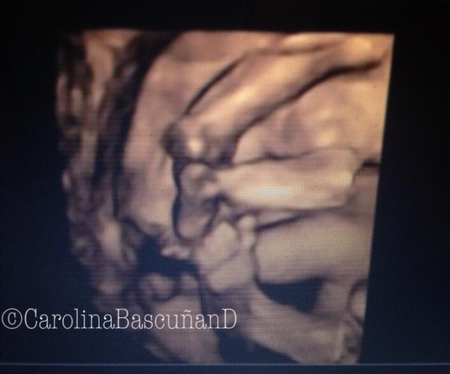

" data-orig-size="1536,1278" sizes="(max-width: 450px) 100vw, 450px" aperture="aperture" />El embarazo iba muy bien (20 semanas de embarazo). Mis chiquititos crecían sin problemas y la mamá podía seguir haciendo sus cosas tranquilamente. Hasta que un día en una ecografía a las 20 semanas, mi ginecólogo descubre que el cuello del útero se estaba acortando muy rápido. Solución, reposo absoluto! Y absoluto es Absoluto, solo tenía permiso para ir al baño y volver a mi cama. Así pasaron las semanas, hasta que en la semana 32 de embarazo la naturaleza ya quiso distinto, y estábamos a horas de transformarnos en padres.

" data-orig-size="480,640" sizes="(max-width: 338px) 100vw, 338px" aperture="aperture" />Después de 12 horas de trabajo de parto, pasó lo más espectacular que hemos vivido, ver nacer, parir y pujar a nuestros dos hijos. Nacieron de 32 semanas, prematuros y tuvieron que estar en incubadora por un mes,